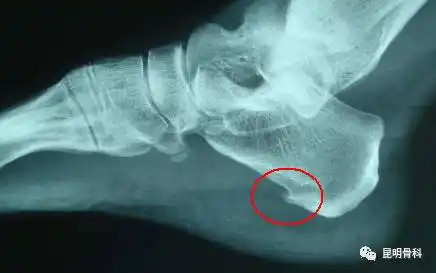

左脚x光片显示跟骨刺呈红色.

跟骨骨刺

顽固性足跟痛-跟骨骨刺-手术治疗 - 好大夫在线